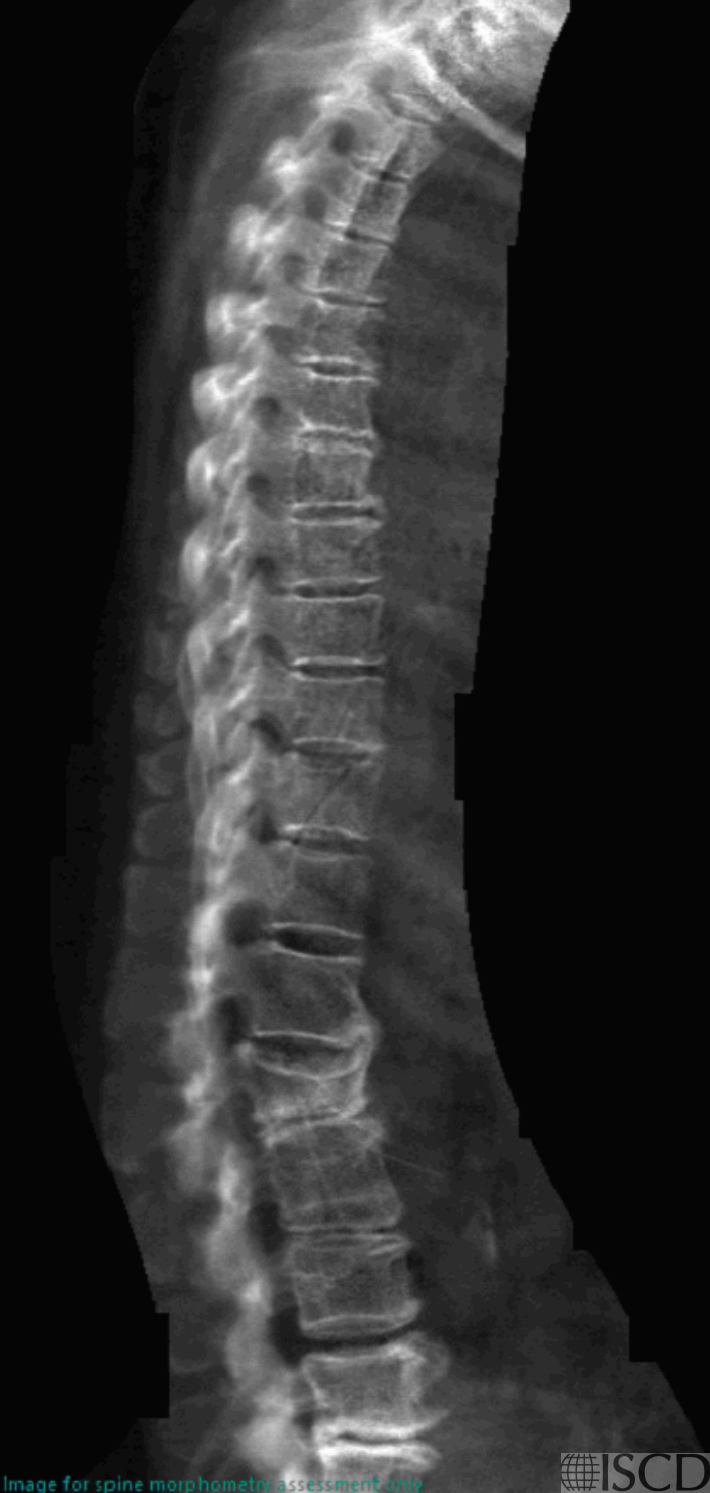

VFA shows a severe L2 compression fracture, new since 2010.